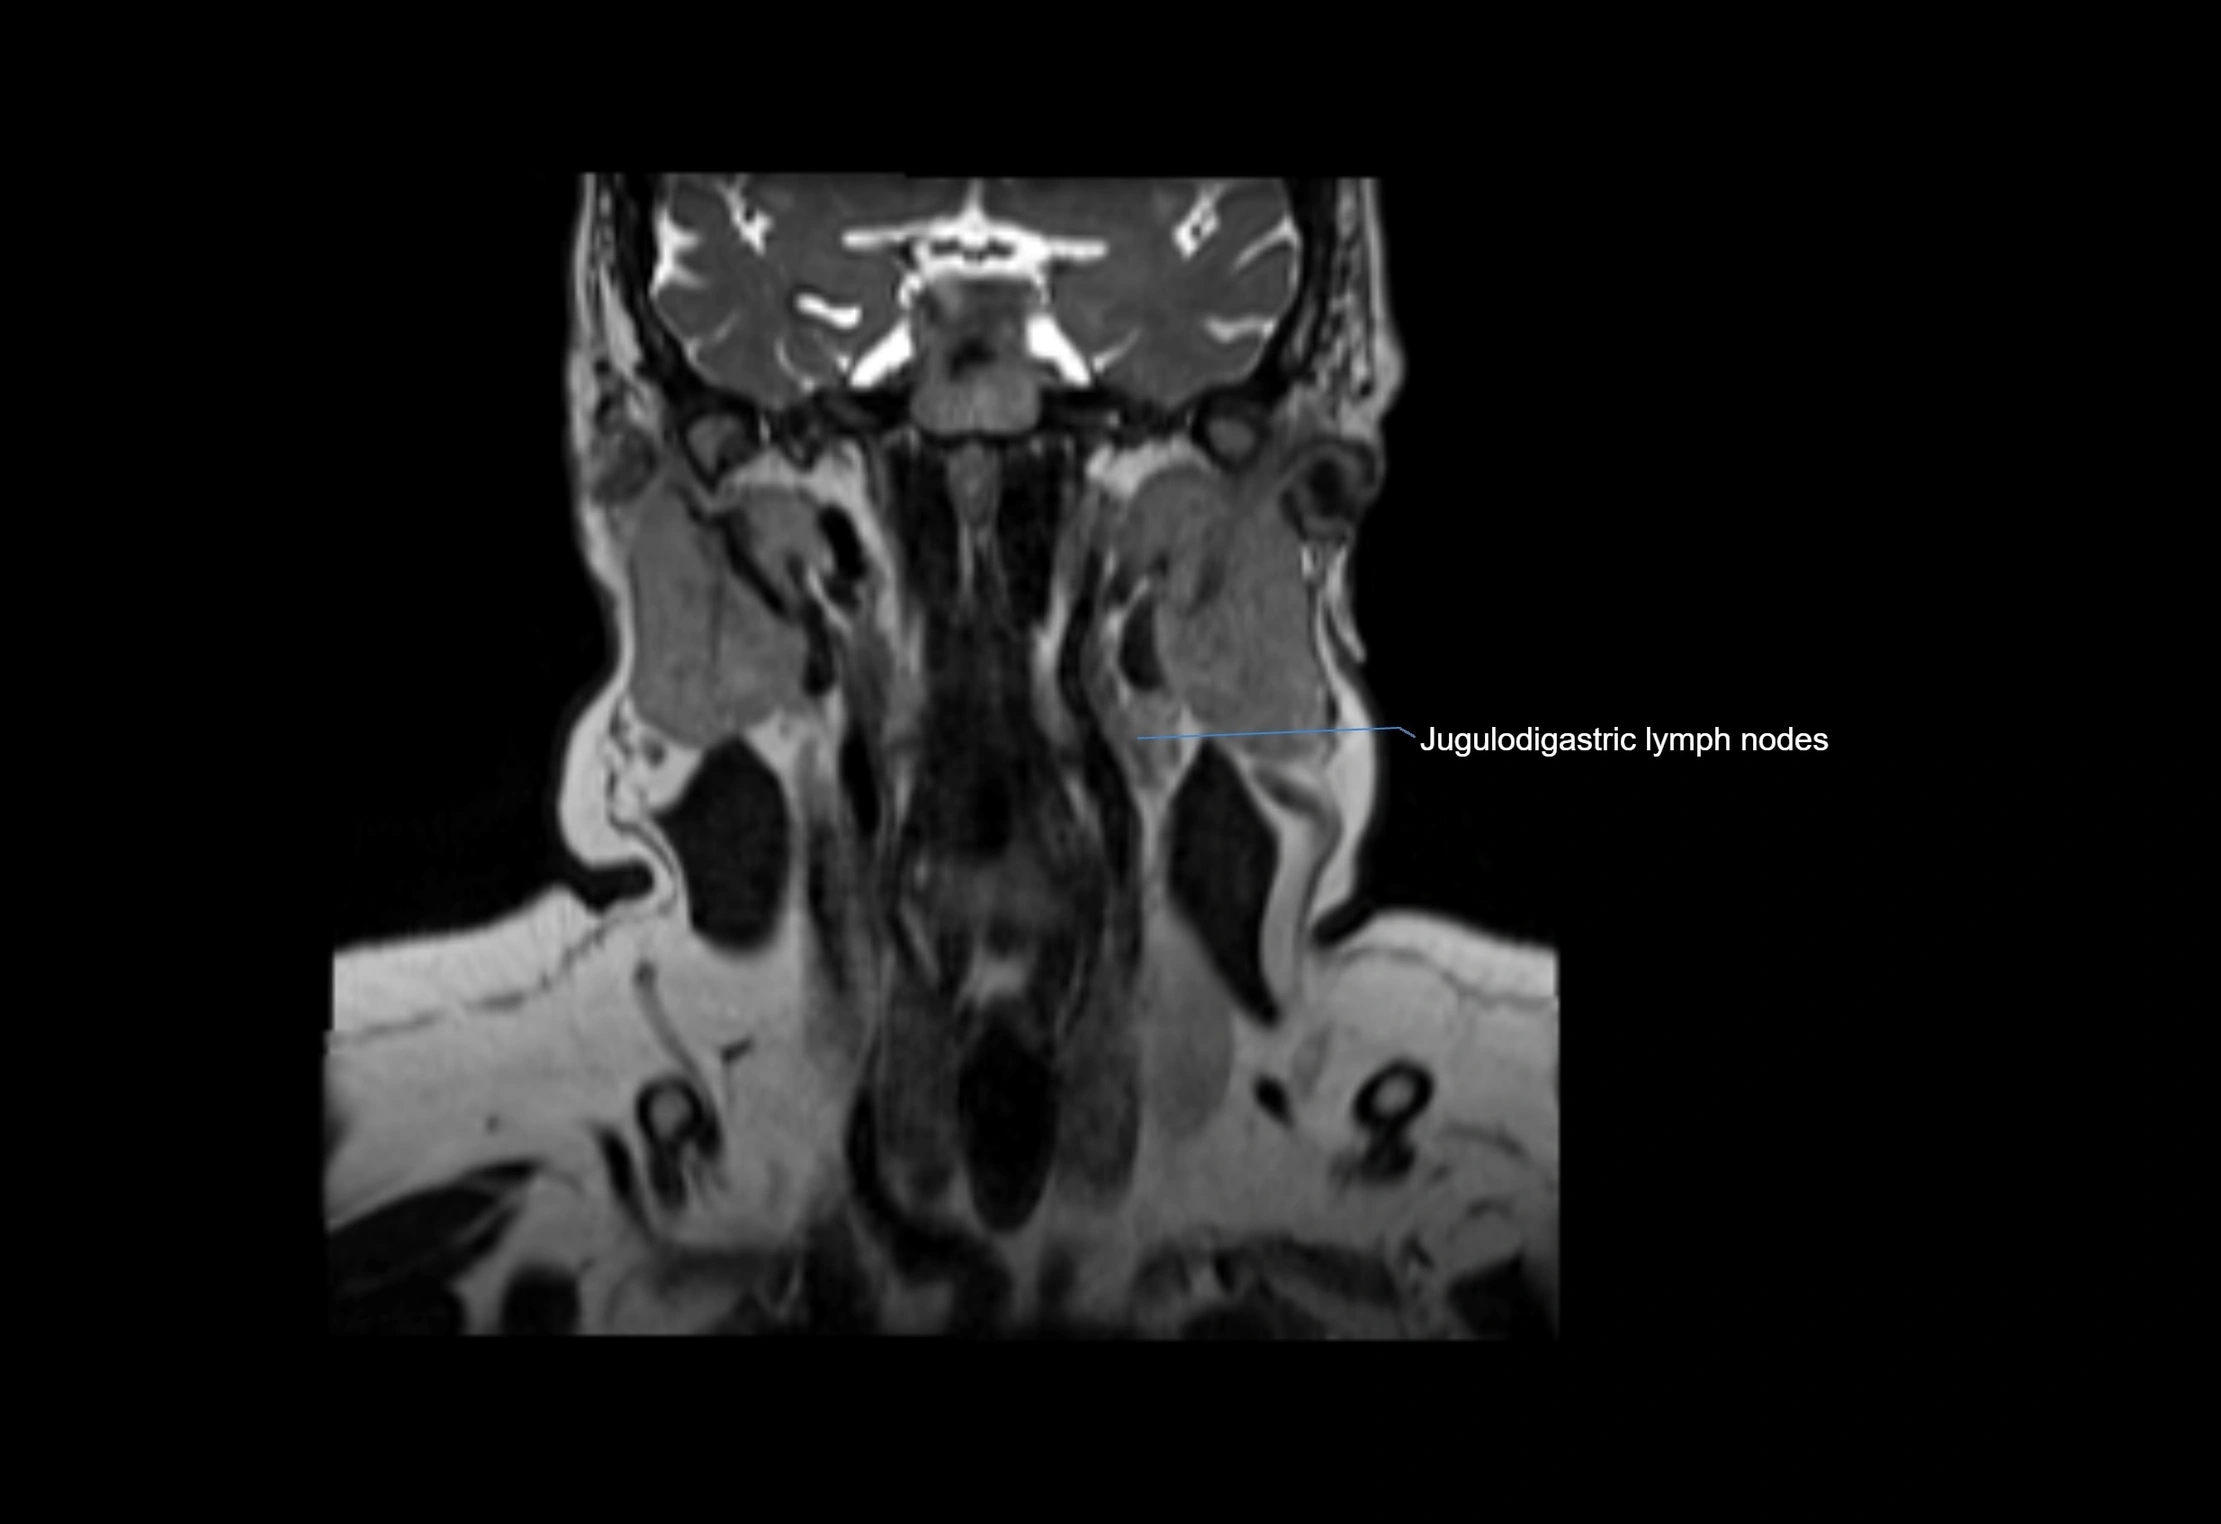

Accessory lymph nodes

Accessory lymph nodes are small, secondary lymph nodes located along the main facial and cervical lymphatic chains, often adjacent to primary lymph nodes, such as preauricular, submandibular, or occipital nodes. They are typically less than 5 mm in diameter, embedded within subcutaneous fat or connective tissue, and may be variable in number and location. These nodes provide additional filtration and immune surveillance for lymph collected from the face, scalp, and neck regions. Accessory lymph nodes are usually non-palpable in healthy individuals but may enlarge in response to infection, inflammation, or metastasis, making them clinically significant.

Location

• Found along primary lymph node chains, including preauricular, submandibular, parotid, and occipital regions

• Embedded in subcutaneous fat or superficial fascia, often lateral or posterior to primary nodes

• Variable in number; may occur unilaterally or bilaterally, depending on individual anatomy

MRI images

image